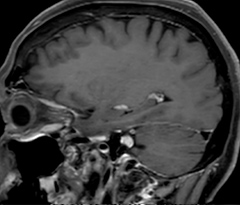

This is an example of acute ischemic stroke with distal occlusion of the right posterior cerebral artery. Note the improved visibility of the ischemic territory on the diffusion weighted image with high b-value. The 3D FLAIR shows a distal PCA occlusion. The fast SWIp depicts the thrombus on the isolated second echo image. The total scan time (including SmartBrain, preparations and a fast 3D T1w TSE Gd) is 8:00 minutes.